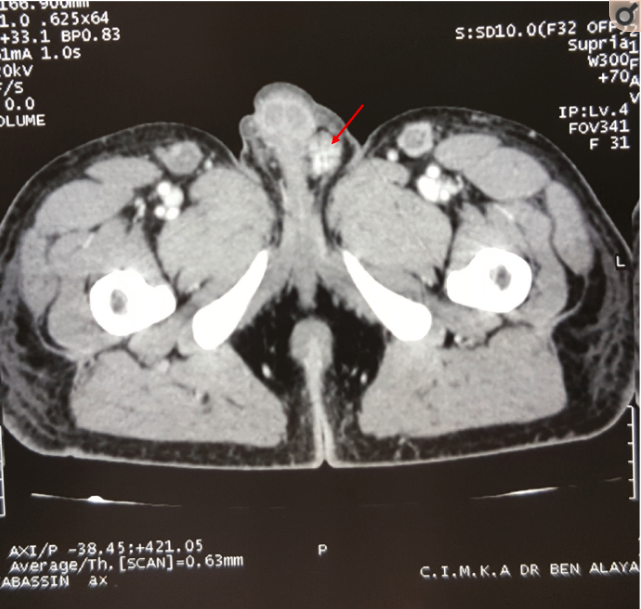

行胸腹部CT检查,提示直乙交接肿瘤狭窄,左侧结节性睾丸,如图1所示。睾丸超声提示左侧异位结节,睾丸鞘膜积液;结肠镜检查提示直肠肿瘤性梗阻。因患者出现腹膜炎体征,行急诊手术,术中见直乙交界肿瘤,横结肠肿瘤,左半肝肿瘤转移,行横结肠肿瘤切除术,结肠双腔造瘘,左侧睾丸切除,肝转移癌活检。术后病理提示结肠腺癌,肝脏病灶与结肠同源,睾丸病理未见睾丸实质,可见癌性增生,仅可见曲细精管结构,如图2。

图1 睾丸左侧混杂密度影,可见结节性睾丸